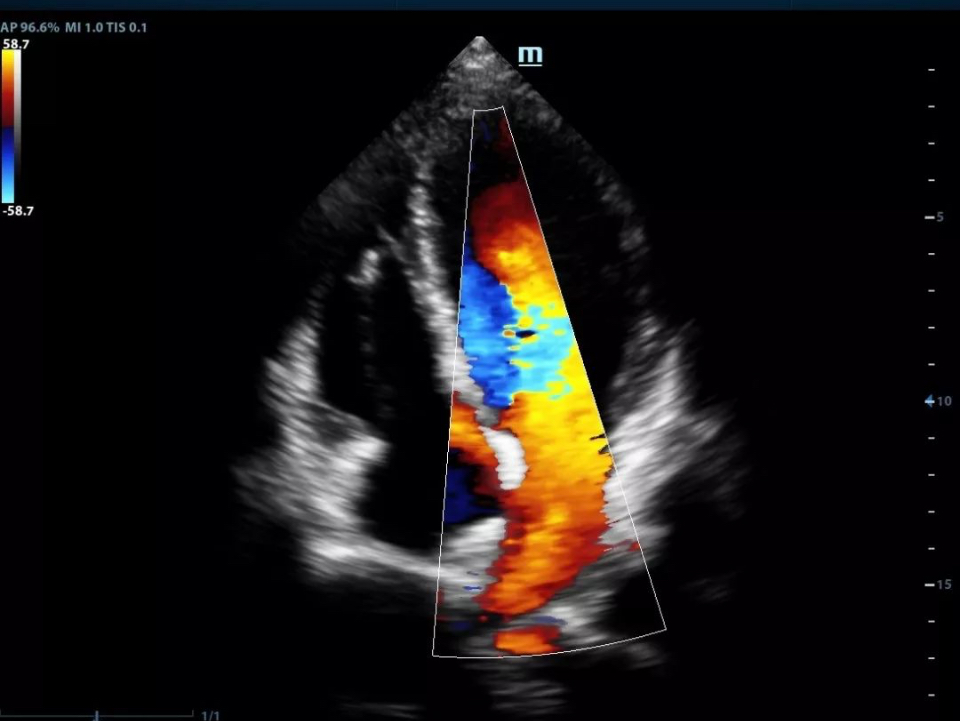

Fetal heart sclerosis

Four chamber view

Single crystal transducers with 3T technology

Mindray's unique single crystal transducers with 3T technology

(Triple-matching layers, Total-cut design and Thermal control) provide a wider bandwidth to simultaneously offer better penetration and higher resolution. Integrating the brand-new single crystal volume, convex and phased array transducers with the system, X-Insight makes an optimum scanning solution in OB/GYN, ABD, Cardiology, and more.